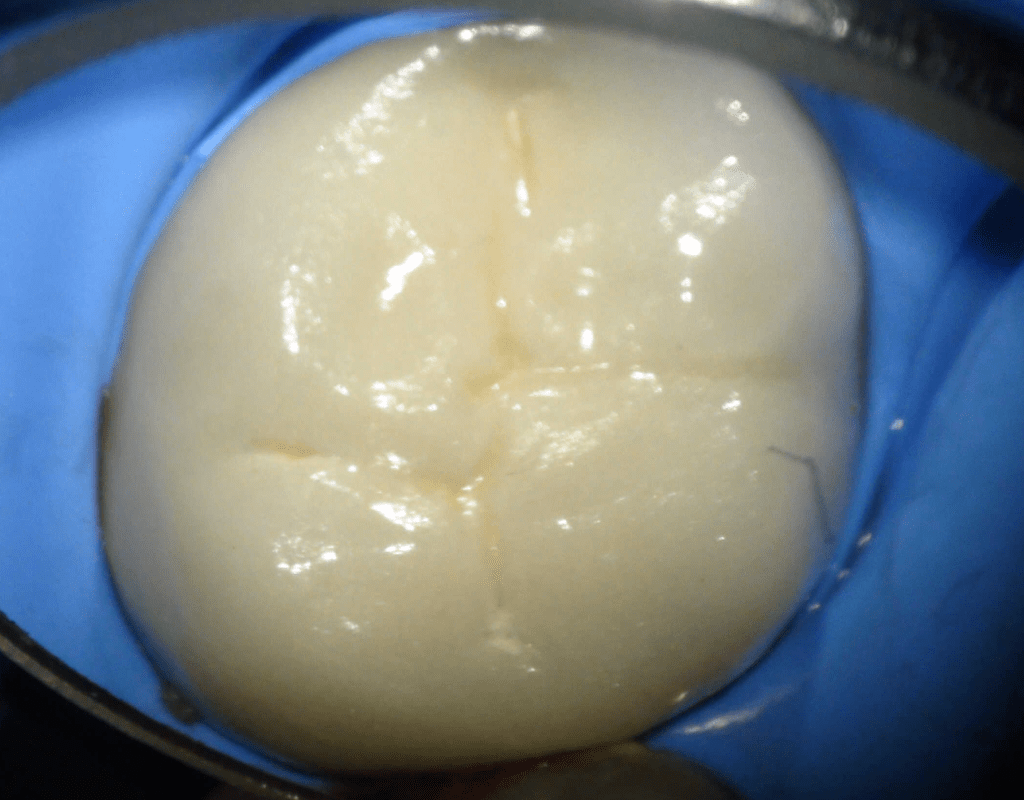

Diagnóstico de fisuras y fracturas

Fisura, remoción amalgama para explorar

Acceso ultraconservador a través de incrustación reciente